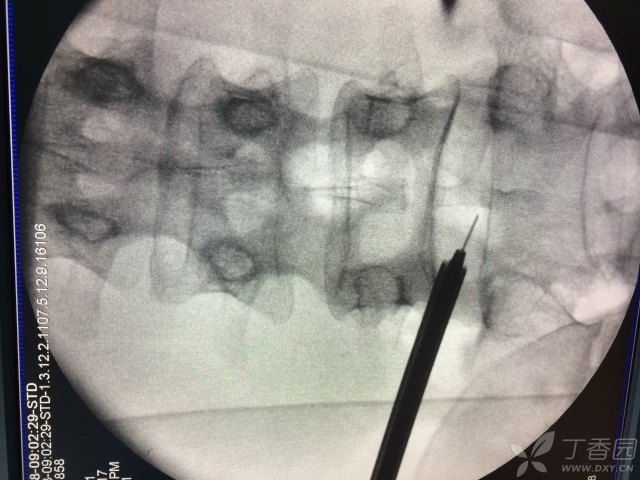

典型病例:椎间孔镜手术治疗巨大腰椎间盘突出

451x600 - 43KB - JPEG